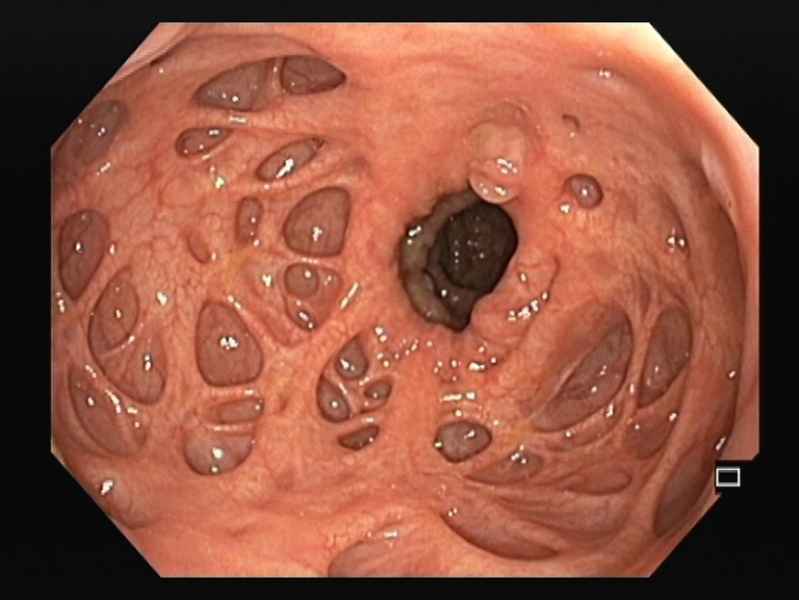

Idiopathic chronic pneumatosis intestinalis: a rare incidental endoscopic finding

Fotografias